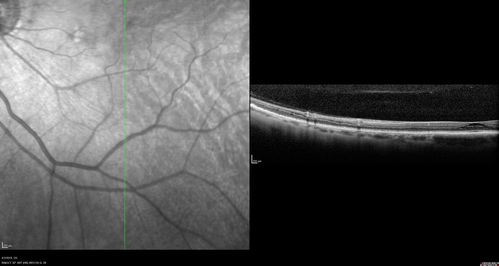

Stellate Non-heredtiary Idiopathic Foveomacular Retinoschisis (SNIFR)

77 year old man who is healthy and 6'6" tall with 20/40 vision and no complaints. OCT shows diffuse retinoschisis.